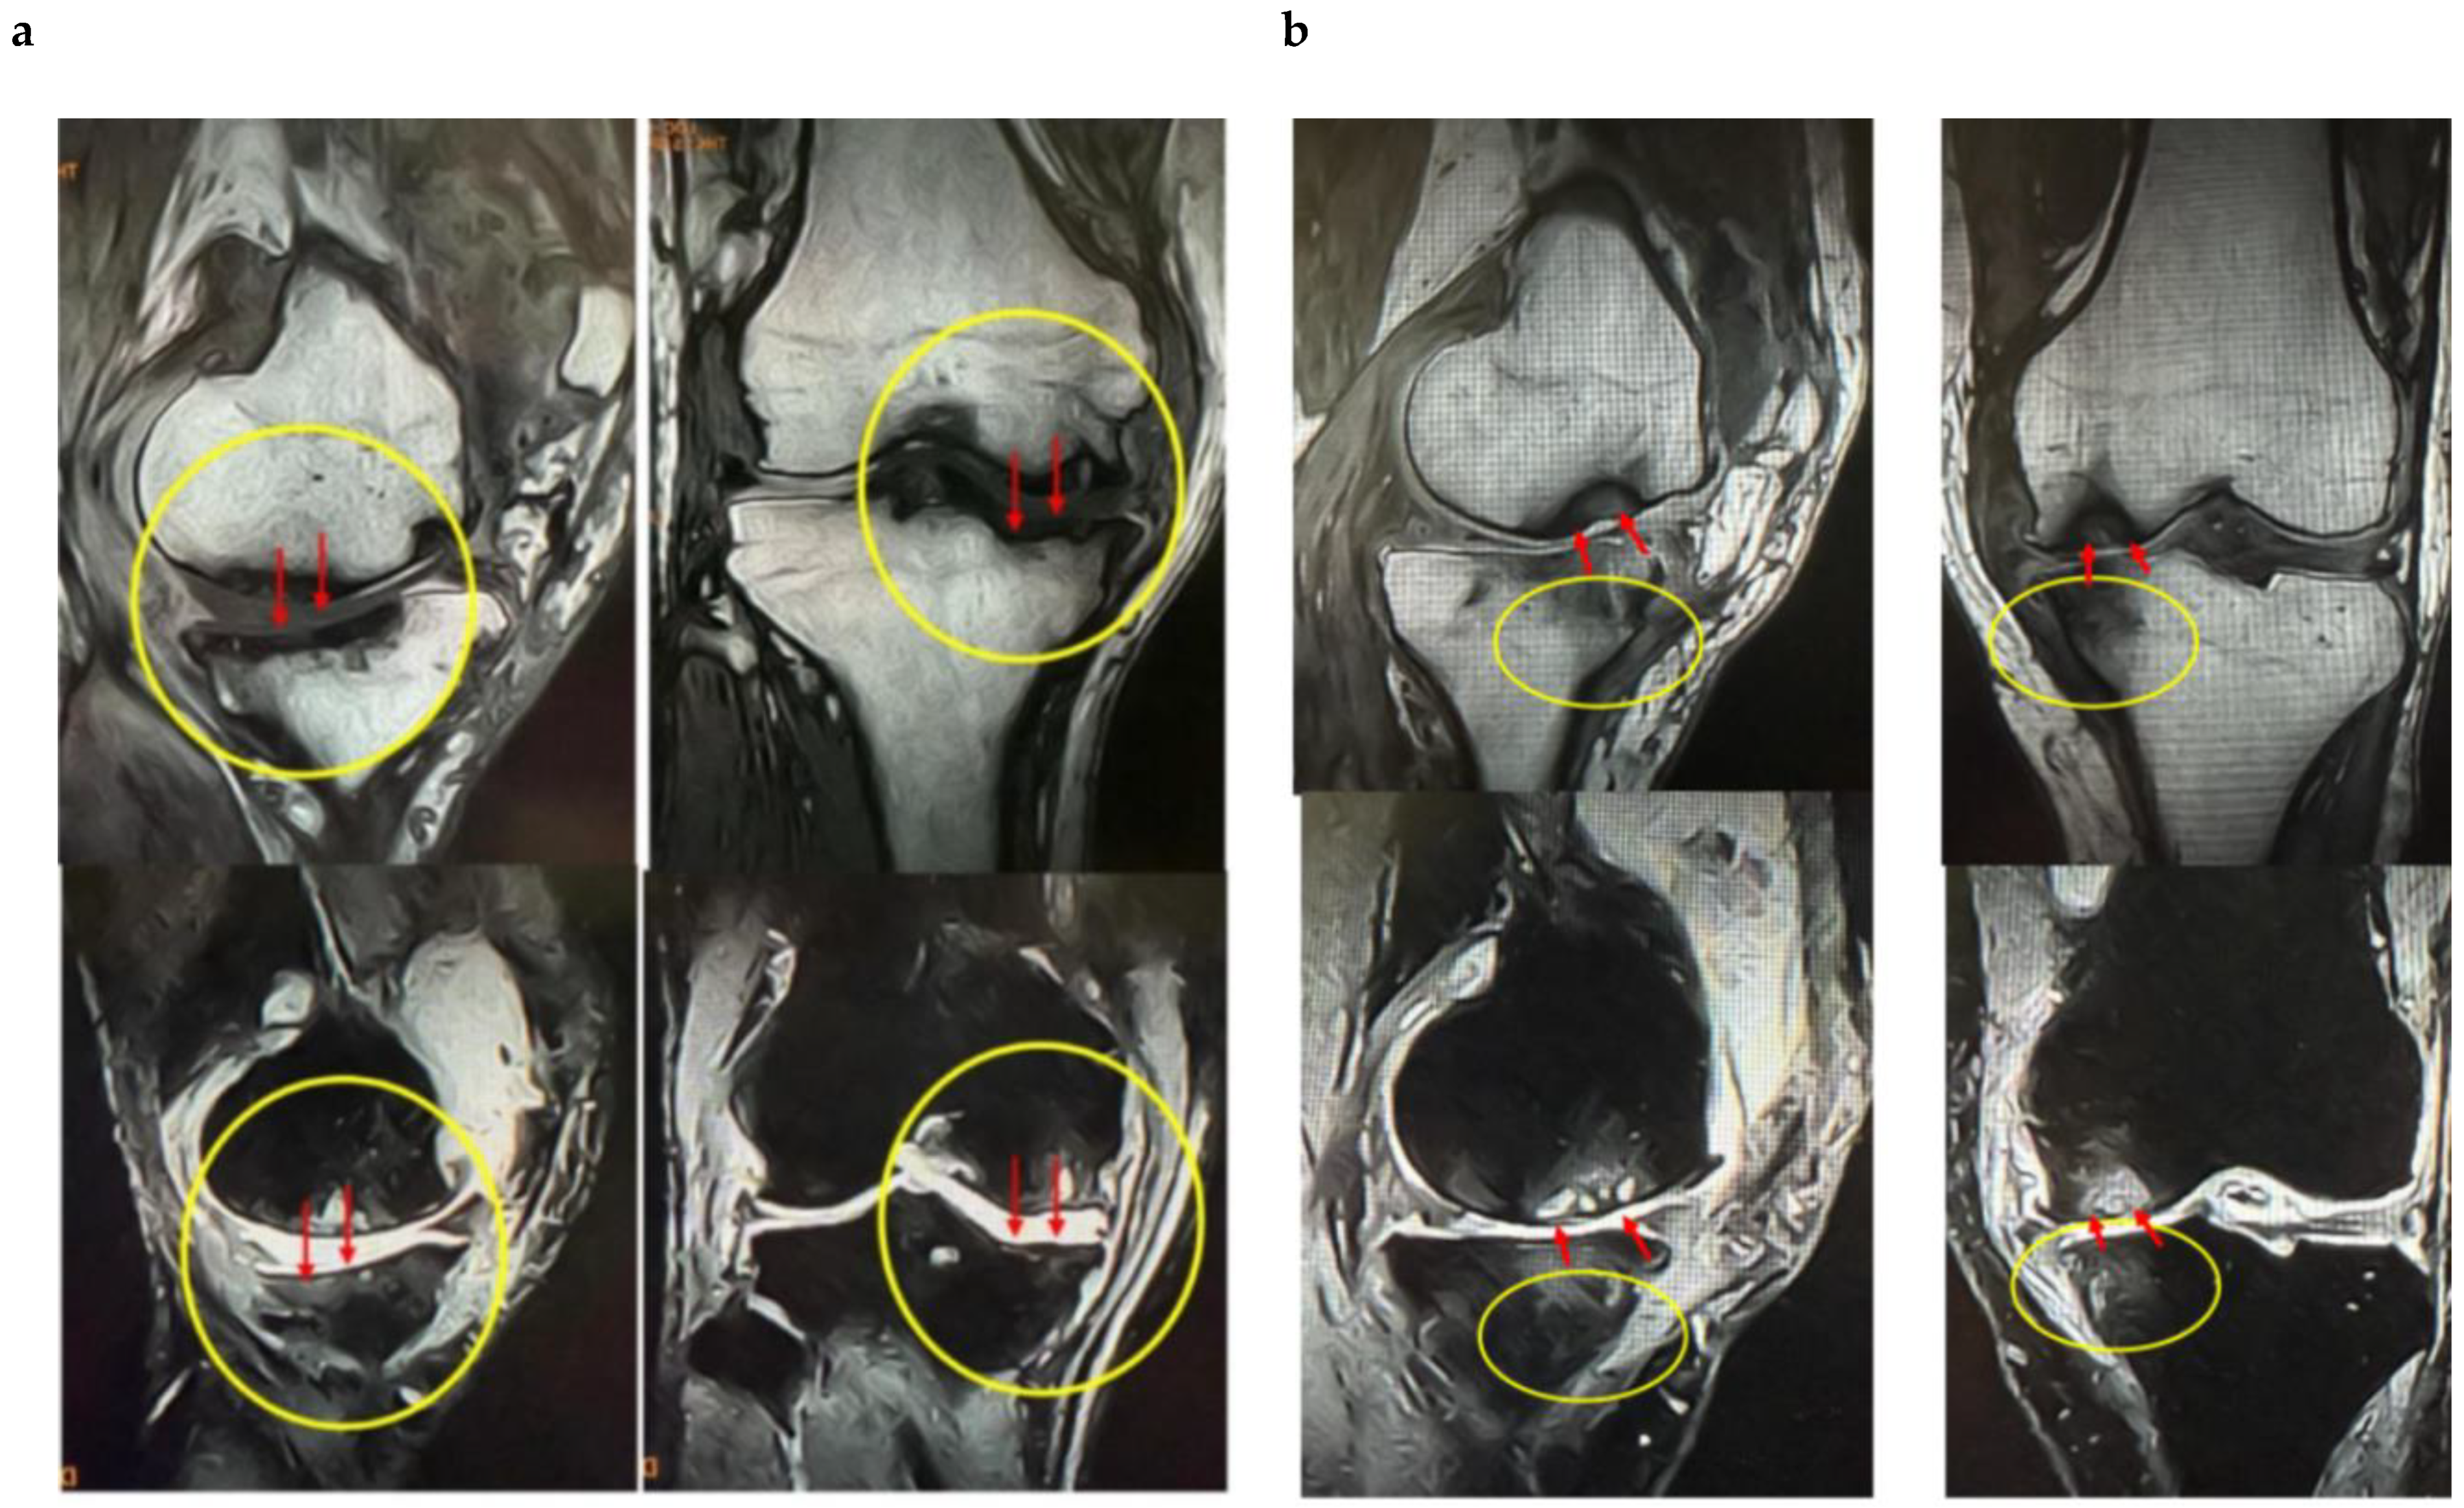

These findings indicate that SBP tear plays a decisive role in BML severity and pain mechanisms, suggesting its importance as a pathological marker in designing knee OA treatment strategies based on BMLs. Consequently, in our conservative treatment strategies targeting subchondral bone, we have prioritized the presence or absence of SBP tear and joint surface collapse (Figure 2a,b and Figure 3a,b).

Figure 2.

Imaging findings of normal and ruptured subchondral bone plate (SBP-tear). (a) Magnetic resonance imaging (MRI) findings of normal and ruptured subchondral bone plate (SBP-tear). Coronal sections of the knee joint are shown on T1-weighted (left) and T2-weighted (right) images. The SBP appears as a low-signal band, similar to cortical bone. The normal SBP, indicated by yellow arrows, demonstrates preserved continuity and a smooth contour. In contrast, the areas marked with red arrows show apparent disruption and irregularity of the SBP. Notably, on T2-weighted images, the presence of joint fluid signal extending into the marrow cavity suggests SBP disruption. (b) Evaluation of SBP disruption using MRI and computed tomography (CT). The left upper panel shows a T1-weighted MRI image, the left lower panel shows a T2-weighted MRI image, and the right panel presents a coronal CT image. In the MRI images, the areas indicated by yellow arrows demonstrate a clear loss of SBP continuity (SBP-tear). On T2-weighted images, the disruption is more distinctly visualized owing to the contrast with joint fluid signals. When the detection of SBP tear is challenging on MRI, CT imaging can provide clearer visualization of the cortical tear in the SBP.